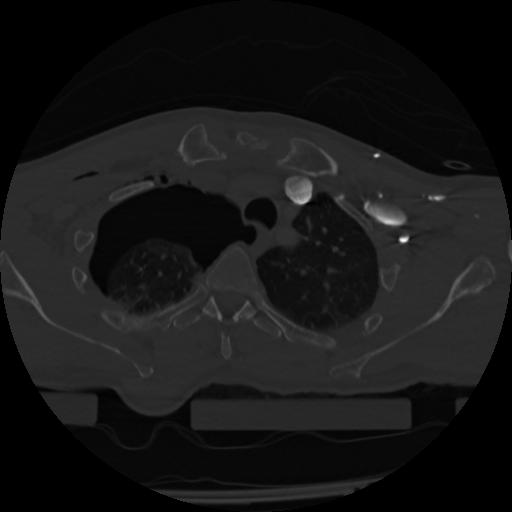

22 ANGIO,CE,Vol,0.5,ANGIO,,